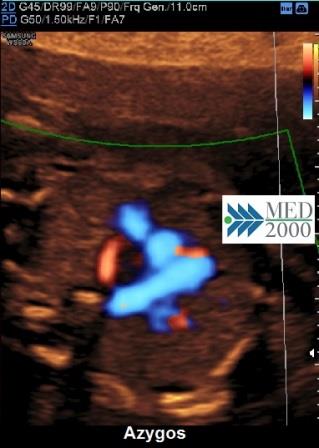

In questa scansione (arteria polmonare più vicina alla sonda) l'ARSA si presenta come un vaso colorato in blu che origina a 90° dalla base della V per dirigersi, passando dietro la trachea, verso la spalla destra del feto.

Se per la posizione del feto l'immagine a "V" è posta in modo che è l'aorta ad essere più vicina alla sonda, l'ARSA assume la colorazione in rosso.

In questa posizione è possibile confondere l'arteria succlavia aberrante con l'azygos. In tal caso la diagnosi differenziale tra i due vasi è possibile per due segni:

- l'origine dell'azygos non è all'apice della "V"

- l'azygos è connessa alla vena cava superiore